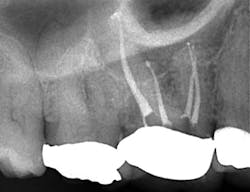

Then, with the same rotary handpiece, I am able to cut final shapes in most molar canals with just one or two GT Series X Files (DENTSPLY/Tulsa Dental Specialties) (Fig. 2).